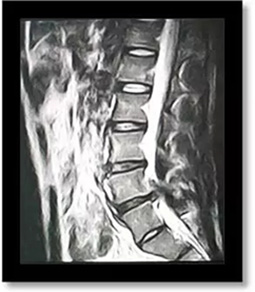

(術(shù)前)

劉志安副院長(zhǎng)經(jīng)查看MRI(核磁共振成像)結(jié)果后,顯示小姚腰5/骶1椎間盤(pán)突出,髓核左下方游離,情況已經(jīng)比較嚴(yán)重,遂收住入院。